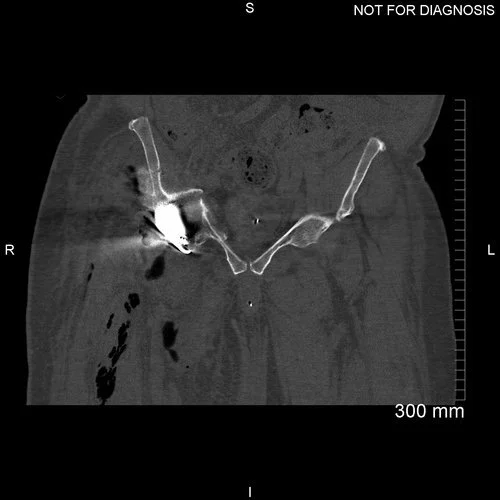

Anteroposterior plain radiograph showing collapse of the acetabular bone around the cup one day post-operatively.

Coronal CT showing minimal bone around the acetabular component.